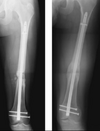

• Classificação de Judet & Judet (modificada por Weber e Cech) (2):

A

• Atrófica (avascular) → não consolida sem intervenção

• Cunha de torção - asa que consolida apenas 1 lado

• Cominuta - fragmentos intermediários necróticos

• Defeito ósseo - perda de segmento, extremidades viáveis

• Ponta de Lápis (atrófica)

• Hipertrófica (hipervascular) → viabilidade biológica (falta de estabilidade)

• Pata de elefante - calo exuberante → falta estabilidade

• Pata de cavalo - calo discreto → falta estabilidade

• Oligotrófica - calo ausente → má redução